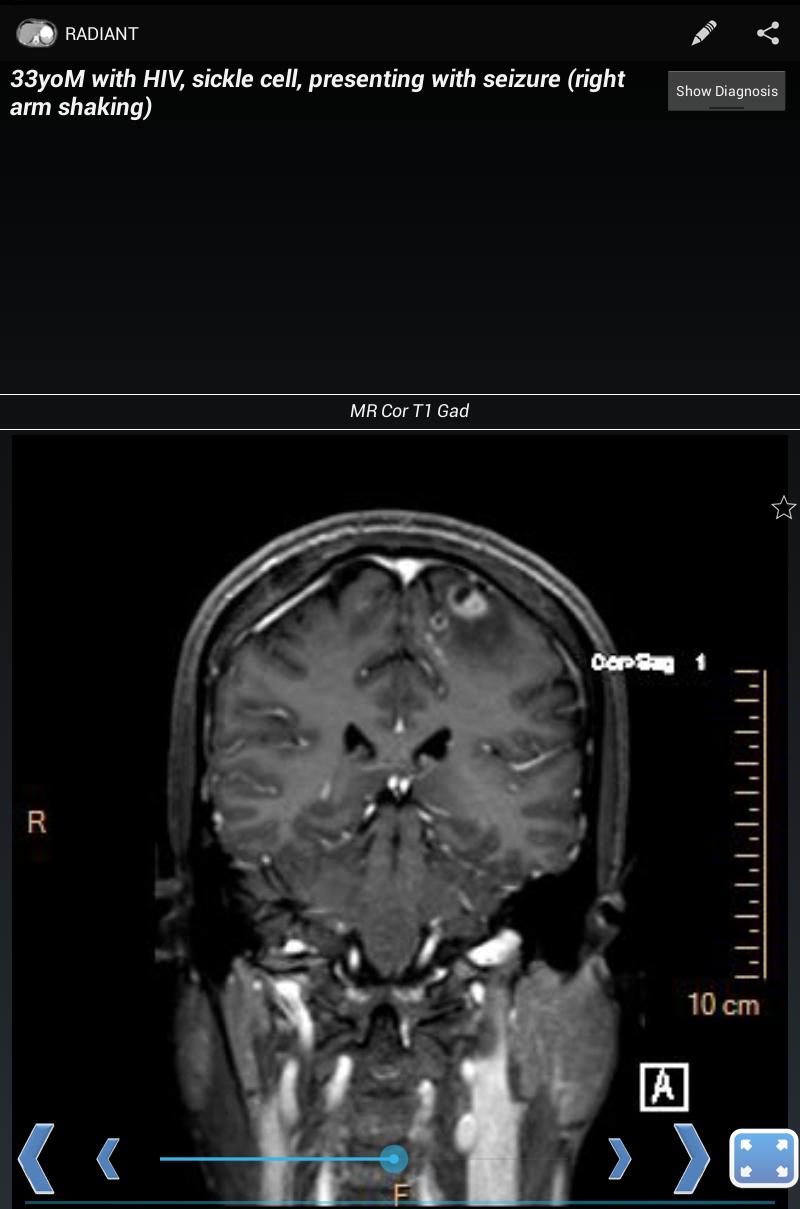

Radiantは、主に医療分野のユーザー向けの画像ベースの教育資料を作成、管理、共有するプラットフォームです。診断放射線科の住民、仲間、医学生、教員の間で興味深いケースを共有するのに最適です。診断に使用することを意図したものではありません。

コンテンツは、基本コンポーネントとして単一の画像を中心に編成されています。複数の関連画像では、画像スタックをスクロールできるシリーズで構成されています。これらの画像シリーズは、ケースのビルディングブロック(1人の特定の患者の特定の診断の画像所見を示す関連シリーズ)、ファイル(テキストブックのような章や章で編成されたトピック)、およびテスト(関連する画像シリーズとのリンクされた質問)を形成します。ケースはケースパックにグループ化できます。ケースパックでは、作成するのに数秒しかかかりません。最後の不明なケースプレゼンテーションや集中的な勉強に最適です。

放射を使用すると、X線、超音波、CT、MRI、またはその他のイメージングモダリティを示すケースを作成できます。これは、実際の高品質の診断医療画像を使用して、胸部X線、正常な解剖学、および一般的な疾患プロセスを学ぶのに最適な方法です。